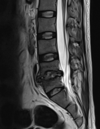

Fratura compressiva da coluna lombar

Causa achatamento do corpo e acunhamento geralmente anterior.

Tipo mais comum de fratura da coluna lombar

Estável.

Mecanismo flexão anterior ou lateral